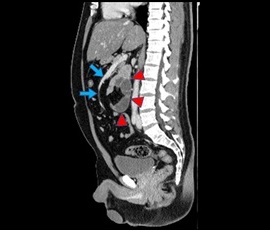

[内ヘルニア(傍十二指腸ヘルニア)] 手術:腹腔鏡下ヘルニア手術

CT画像